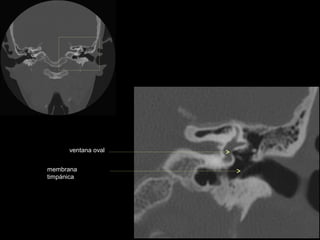

CATEDRA DE RADIOLOGIA U.N.L.P.   Hueso temporal normal        Edición 2002

ventana oval

membrana

timpánica

conducto semicircular

externo

superior

antro mastoideo

ventana redonda

nervio facial (3era)

conducto semicircular externo

conducto semicircular superior